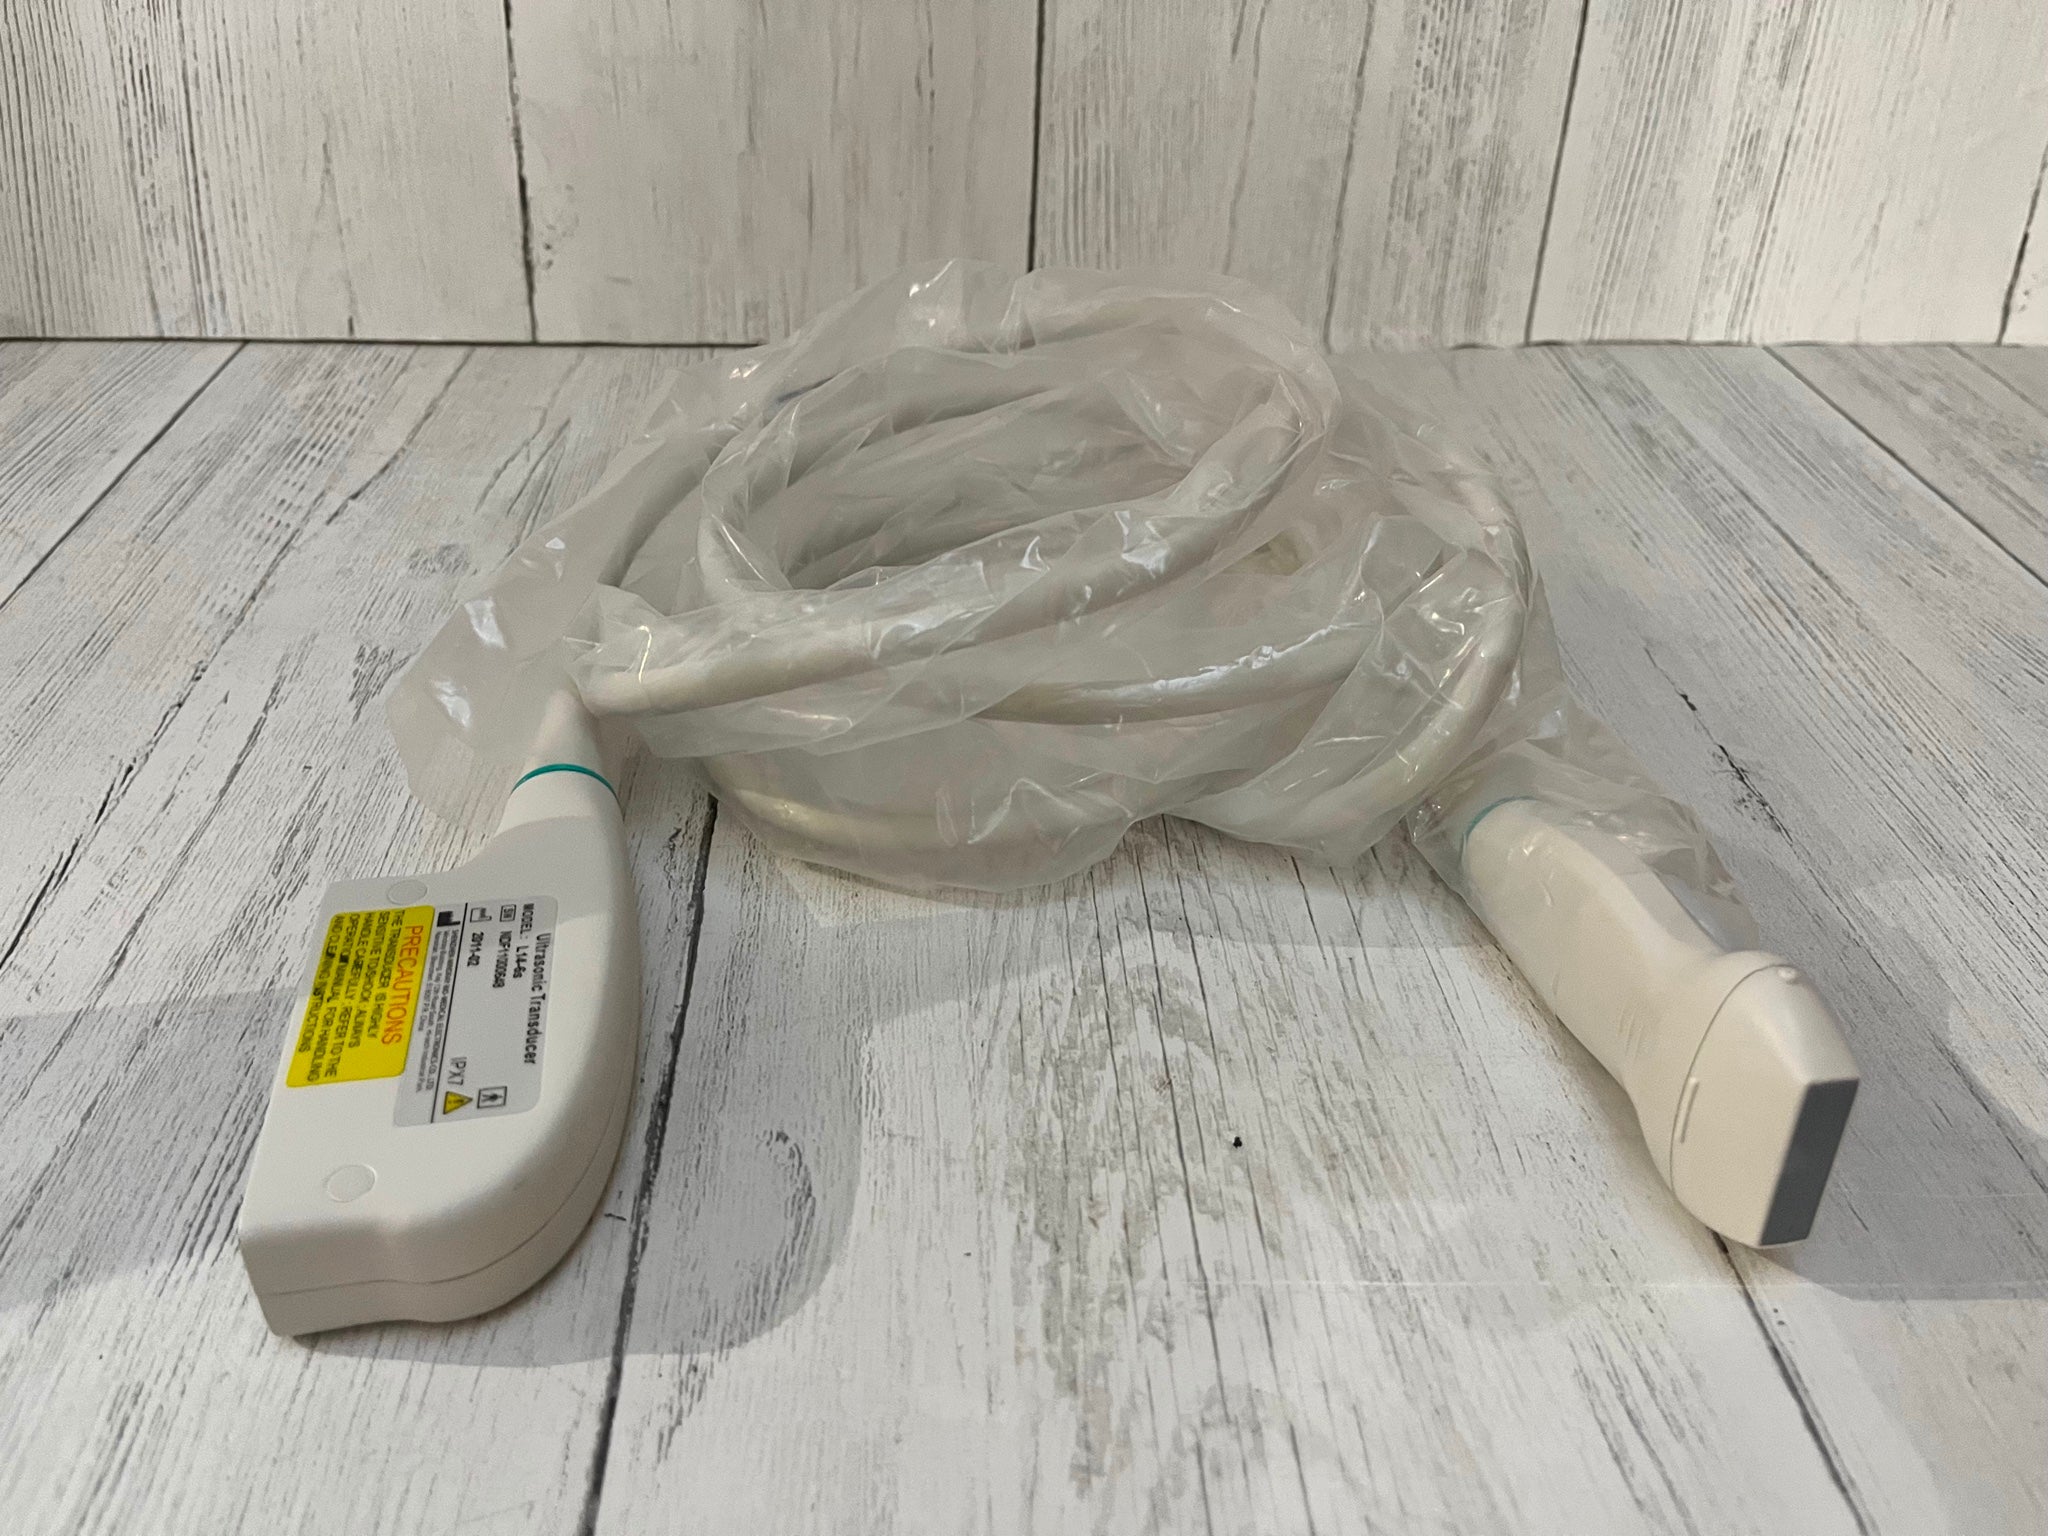

Ultrasund Probe Transducer TOSHIBA PLT-704ST

Sale price$ 3,344.48